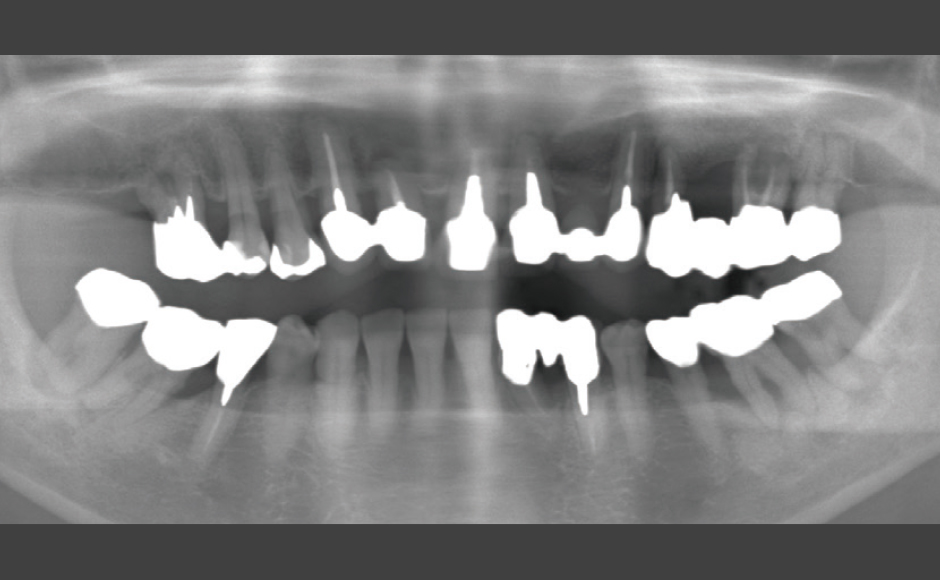

歯周病および根尖病巣により骨吸収、動揺が激しく、抜歯適応の歯牙に対し非外科的に歯周治療をNd:YAGレーザーを用いて行い、歯牙の保存を試みた症例